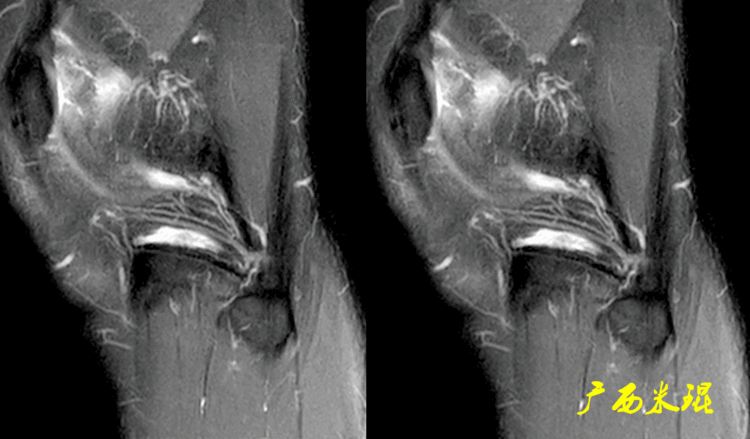

3、从邻近病变诊断半月板损伤城门失火、殃及鱼池,孤立性的损伤/疾病都是不多见的,我们可以通过半月板邻近的改变来反推是否有半月板损伤,下面这张MR我们看见外侧半月板前角有一个较大的囊肿,而半月板囊肿的起因一般都是半月板损伤,所以也很容易做出诊断。